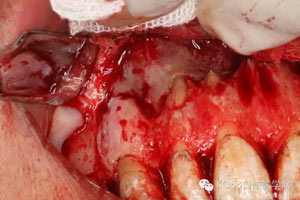

圖4.翻瓣、去除覆蓋在囊腫表面骨質,暴露出囊壁。